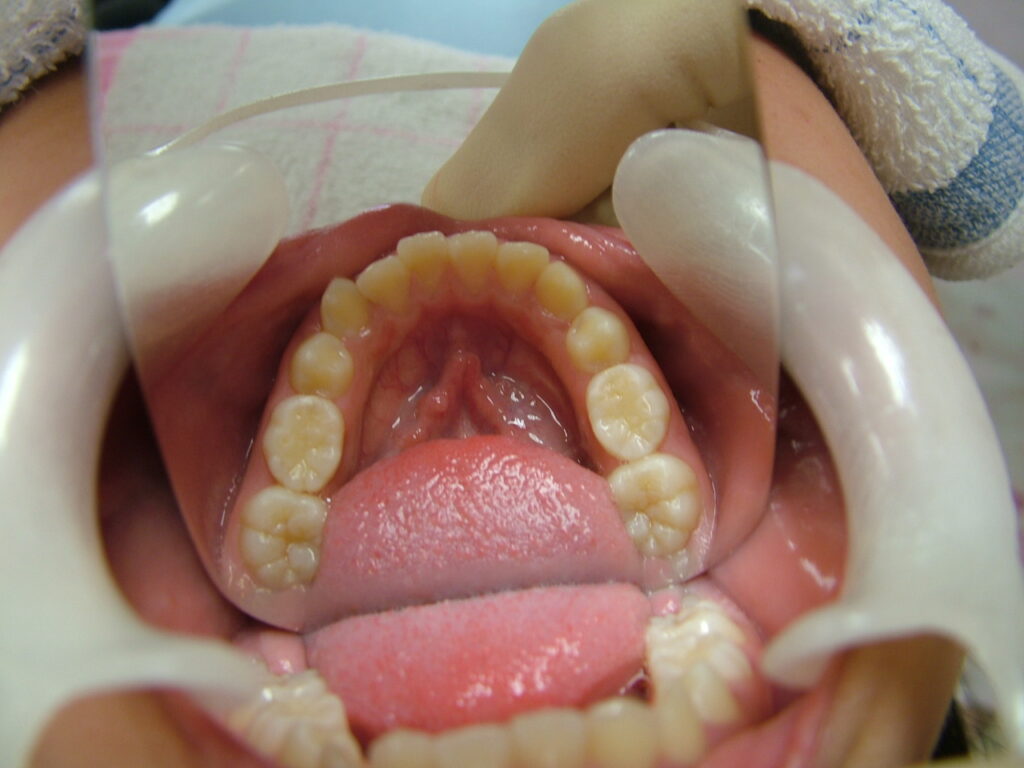

治療後

治療後のコメント

虫歯や歯肉炎の発症なく、まずまずの状態で1期治療を終了したと思います。もう少し上下顎拡大も考えましたが口が大きくなることを考慮して、最小限のディスキングで対応しました。親御さん、子供さん共に非抜歯での矯正を希望されましたが、今後シャープな口元を希望される場合、矯正の専門医で小臼歯4本抜歯ワイヤー矯正されるのも良いかもしれません。しかし舌房が狭くなり、噛みしめが誘発された方(歯周病の悪化、肩こり、知覚過敏、不定愁訴等)を数多く見てきているため、私は成人抜歯矯正(2期治療)をやるつもりはありません。(注、私は全ての抜歯矯正を否定しているわけではありません。正しく舌房の確保、舌のポジション、上下7番のコントロールを考えた矯正医が行うのは素晴らしいと思っています。)